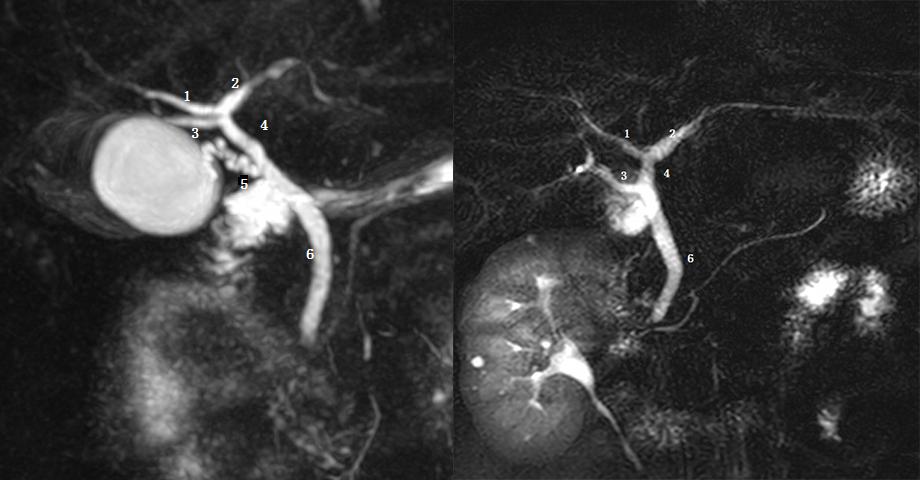

Ⅰ型:肝左右管汇合肝总管,胆囊管与肝总管汇合胆总管。左图:1 为肝左管,2 为肝总管,3 为胆囊管,4 为肝右管,5 为胆总管。黑箭头为胆囊结石。

图为胆总管结石继发梗阻患者。Ⅱ型:肝右前、右后肝管与肝左管汇合肝总管,呈三叉状,1 为肝右前肝管,2 为右后肝管,3 为肝左管,4 为肝总管,箭头为肝总管及胆总管结石。